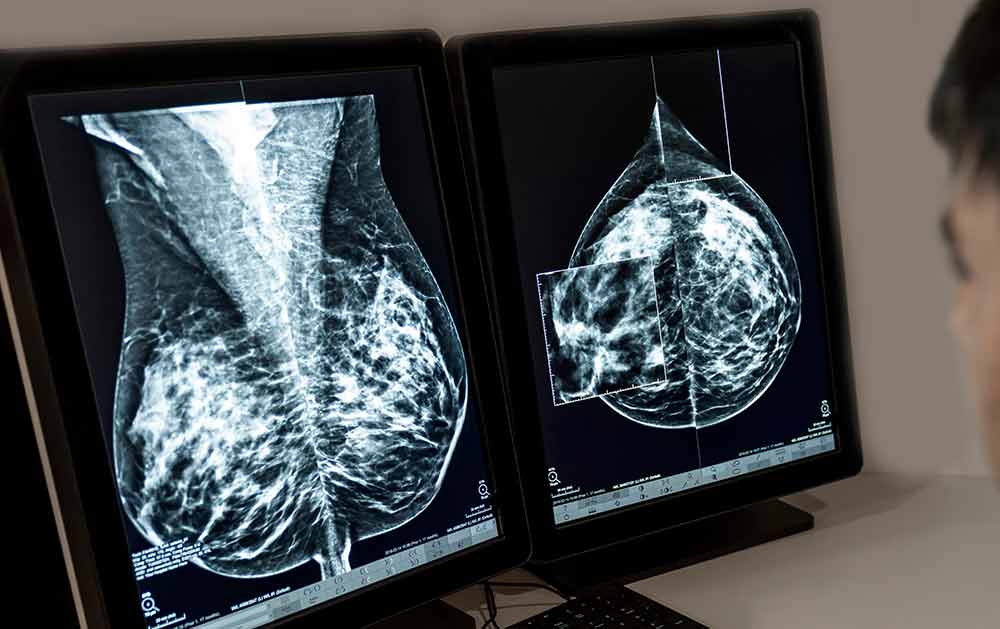

The most comprehensive cancer-specific screening available. Combining high-resolution Full Body MRI detection of solid tumours with the revolutionary Trucheck™ blood analysis for over 70 types of circulating tumour cells.